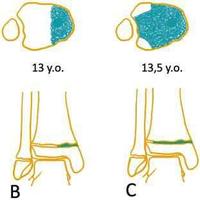

Tillaux 骨折是累及胫骨远端骨骺的

Tillaux 骨折是累及胫骨远端骨骺的关节内骨折,约占所有胫骨远端骨骺损伤的 2.9%。单靠 X 片容易漏诊,一旦误诊或漏诊导致踝关节不匹配、不稳定,患者会遗...